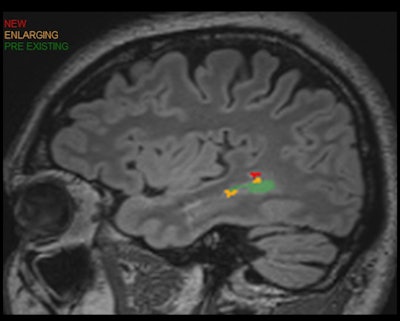

Segmentation is one of AI's natural capabilities and is useful in the brain and the spine, according to Tanenbaum. For example, AI can assist in assessment of multiple sclerosis (MS) by counting lesions and assessing change in both the size and number of lesions, he said.

AI can also identify new lesions and show which lesions are bigger and which ones are smaller, Tanenbaum said.

Several studies in the literature have shown that AI-assisted software for quantitative neuroimaging and MS can standardize and speed reporting, as well as enhance sensitivity.

Lesions changes can also be correlated with treatments on a report, enabling rapid assessment of treatment response.